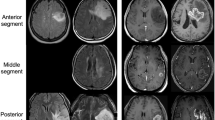

In the study group, language lateralization based on hemispheric LI demonstrated 212 LL and 193 AL patients. Frontal LI demonstrated 217 LL and 188 AL patients. Broca’s LI demonstrated 236 LL and 169 AL patients. Temporal LI demonstrated 222 LL and 183 AL patients. Wernicke’s LI demonstrated 217 LL and 188 AL patients. Laterality results according to tumor type are reported in Table 3. Two representative cases are displayed in Fig. 2. The distribution of the five LIs is presented in Fig. 3. The age distribution of AL and LL patients according to the calculated LIs was not significantly different on Mann–Whitney U test.

Exemplificative cases of language plasticity. Above, fMRI correlation map overlayed on axial post-contrast T1-weighted images of a 67-year-old man with glioblastoma affecting the left, lower-frontal lobe. The fMRI map shows co-dominant activation of Broca’s area (left activation: green arrow in a; right activation: light blue arrow in a). The hemispheric LI of this patient was − 0.32. Below, fMRI correlation map overlayed on axial post-contrast T1-weighted images of a 51-year-old man with glioblastoma affecting the left, lower-frontal lobe. This fMRI map shows left-dominant activation of Broca’s area (light blue arrow in e). The hemispheric LI of this patient was 1